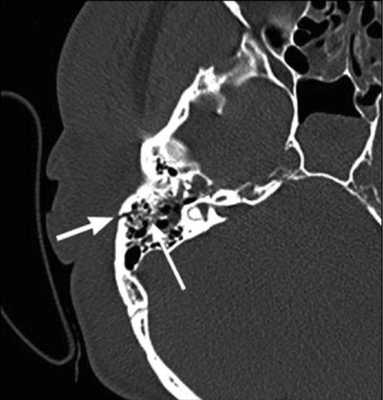

Рис. 1. КТ височных костей пациентки М. а — коронарная проекция: деструктивная полость в пирамиде височной кости, заполненная субстратом неоднородной плотности, капсула лабиринта значительно разрушена на уровне базального и апикального завитков улитки, латерального и верхнего полукружных каналов; б — аксиальная проекция: деструктивная полость с разрушением задней грани пирамиды, передневерхней и нижней поверхности.